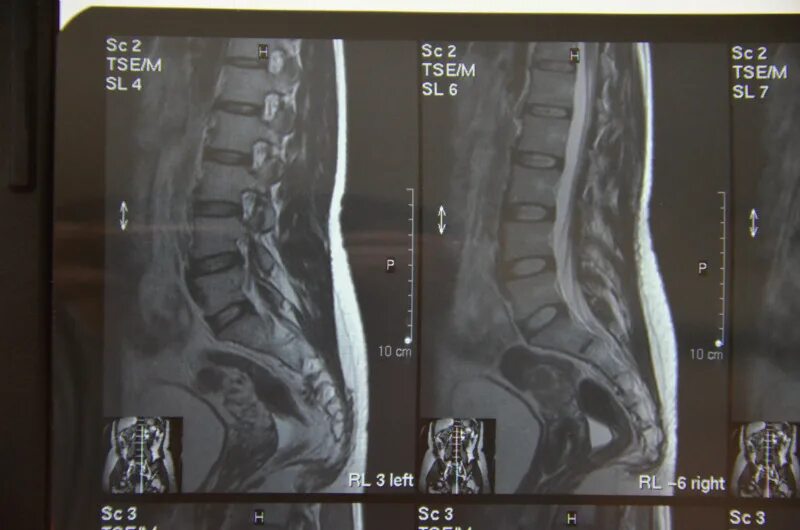

Крестцово-копчиковый отдел позвоночника мрт. мрт пояснично-крестцового отдела позвоночника и копчика.

Кт крестцового отдела позвоночника. кт поясничного крестцово поясничного отдела. крестцово копчиковый остеохондроз. мрт пояснично-крестцового отдела и копчика.

Крестцово-копчиковый отдел позвоночника мрт. мрт пояснично-крестцового отдела и копчика. перелом копчикового позвонка. копчиковый отдел позвоночника рентген.